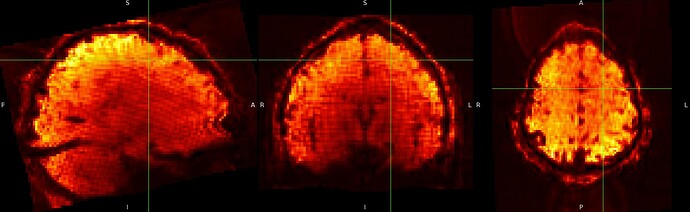

And although it is not visible for the SE sequence in MNI152NLin6Asym-res2, it is visible outside the brain in the ME sequence in MNI152NLin6Asym-res2

SE sequence in MNI152NLin6Asym-res2

ME sequence in MNI152NLin6Asym-res2